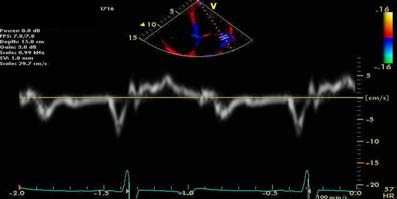

同一患者,间隔侧二尖瓣环E/e'= 80/4 = 20

同一患者,侧壁二尖瓣环E/e'= 80/5 = 16

通常室间隔e'较侧壁的e'低,室间隔的E/ e'较侧壁获得的E/ e'值偏高,基于测量位置及LVEF值不同应采用不同的界线值。

但在目前指南中,鉴于二者速度存在差异,临床中评估E/ e'时,通过测量间隔及侧壁的二尖瓣环e'并取平均值来预测左室充盈压(尤其存在局部功能障碍时必须取平均值)。

一例前间壁心肌梗塞患者的组织多普勒测量图(左为间隔侧,右为侧壁)。注意二者速度不同,应采用室间隔与侧壁e’平均值估测LV松弛性和充盈压。